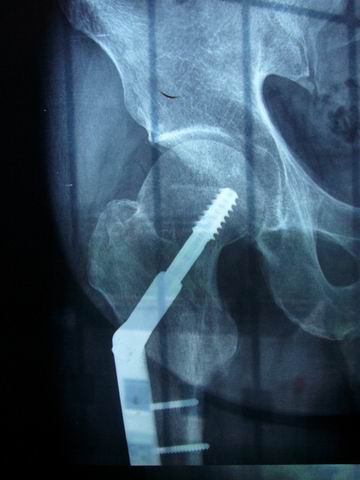

主题:我大腿里取出的钢板-----大家注意安全

07年不幸摔伤,固定骨折安钢板,08年取钢板,不仅经受了痛苦,而且花费了近20000银子,等于损失了一个好自行车,可惜啊!!

图片点击可在新窗口打开查看此主题相关图片如下:p1020986.jpg

图片点击可在新窗口打开查看此主题相关图片如下:调整大小 p1020962.jpg